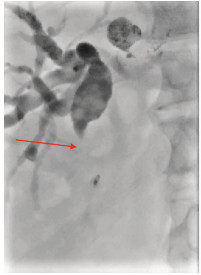

Multidisciplinary treatment of hepatocellular carcinoma with tumor thrombosis in the left portal vein: A case report

Jihong YANG, Guoxiang CHEN, Mo ZHOU, Jisen ZHAO, Yuan WANG, Yuanlong ZHOU

2021, 37(3): 666-679. DOI: 10.3969/j.issn.1001-5256.2021.03.031

Abstract(1233) HTML (573) PDF (3239KB)(76)

Abstract: